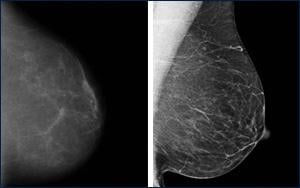

Film vs. Digital Mammography

January 21, 2010 - More than 60 percent of U.S. breast imaging facilities offer digital mammography and more are acquiring digital services each month, and a new study may drive the adoption of digital mammography even further.